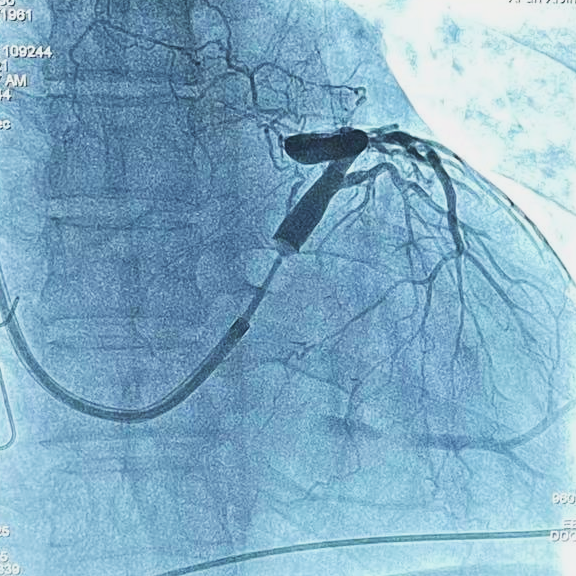

本例患者女性,59岁,扩张性心肌病,QRS波162ms,EF值21%,符合CRT植入的I类适应证。根据该患者的病史及临床症状,刘兵教授团队经过充分的术前评估和准备,拟行CRT-D植入术。此次选用的是波士顿科学X4左室四极CRT-D。

通过术中球囊造影可见,该患者的心脏存在多根可选的靶静脉,沈敏教授分析了每根血管的特点之后,决定选用波士顿科学Acuity X4 Spiral S(型号4674)左室四极导线,首先尝试置入患者的前侧静脉,但由于该静脉相对短且迂曲,左室导线上的四个电极无法完全进入该静脉血管。为了保证最佳的CRT疗效,沈敏教授决定放弃前侧静脉,并尝试植入心后静脉,最终顺利将该左室四极导线推送至静脉远端,固定牢靠,起搏阈值良好,无膈神经刺激出现。该病例充分展示了X4左室四极导线在不同血管中的表现,尤其是Acuity X4 Spiral S左室四极导线上3D立体螺旋在血管近端固定上的优势。

术中造影图像和最终电极位置